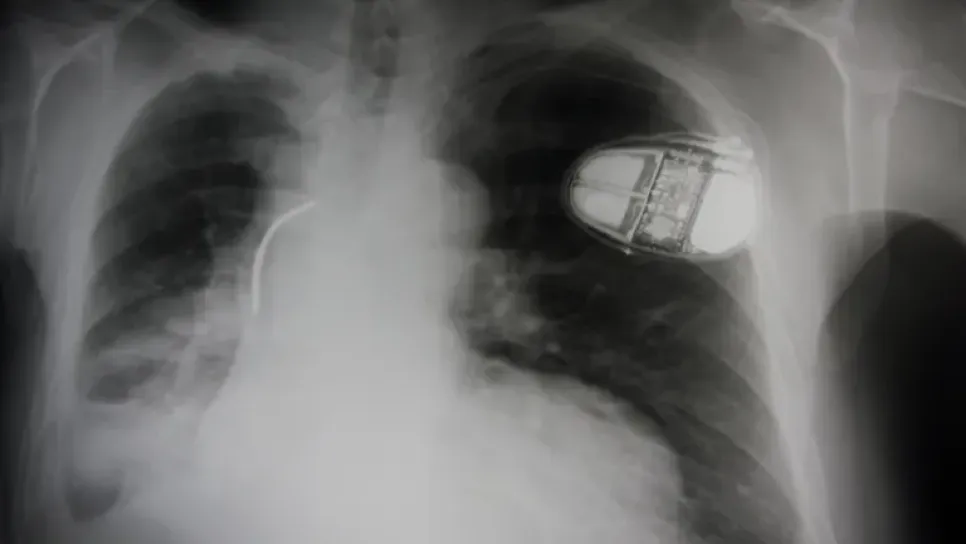

يعمل علماء على جهاز لتنظيم ضربات القلب في المستقبل خال من البطاريات ويمكن أن يعمل بطاقة القلب نفسه. وتتكون أجهزة تنظيم ضربات القلب النموذجية من مولد نبض، يحتوي على بطارية ودائرة كمبيوتر صغيرة، وسلك واحد أو أكثر يعرف بمنظم السرعة، تتصل بقلبك. ويبعث المولد نبضات كهربائية عبر الأسلاك إلى قلبك ويطلق على معدل إرسالها للخارج معدل السرعة. وفي الوقت الحالي، يجب استبدال معظم بطاريات جهاز تنظيم ضربات القلب كل خمس إلى 12 عاما، والقيام بذلك يعني إجراء جراحة في كل مرة. ومع ذلك، يحاول باحثون من جامعة "شنغهاي جياو تونغ" حل هذه المشكلة من خلال تطوير جهاز يعمل على القلب نفسه لتوليد الطاقة -ما يعني أنه لن ي...